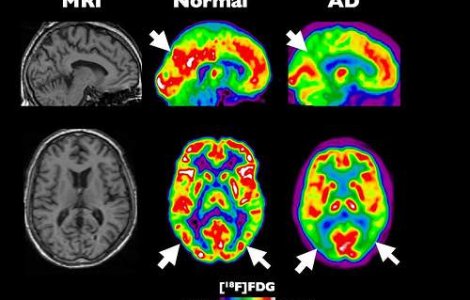

Alzheimer: creierul incepe sa se micsoreze cu 10 ani inainte de diagnosticarea bolii